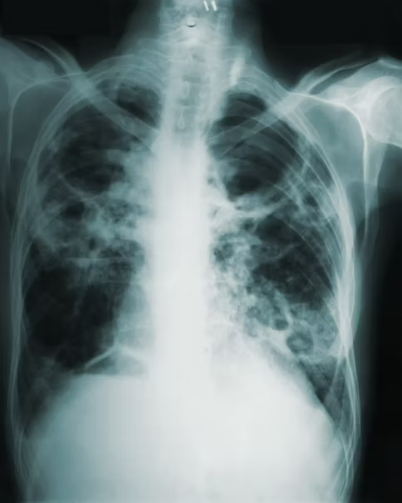

활동성 결핵 환자가 발생한 경우에는 가족이나 직장 동료 등 밀접 접촉자에 대한 결핵 검진과 잠복감염 검사가 이루어져야 합니다. 흉부 X선, 객담 검사, 혹은 결핵감염검사를 통해 감염 여부를 확인하고, 잠복결핵이 발견되면 예방 치료를 병행해야 합니다.